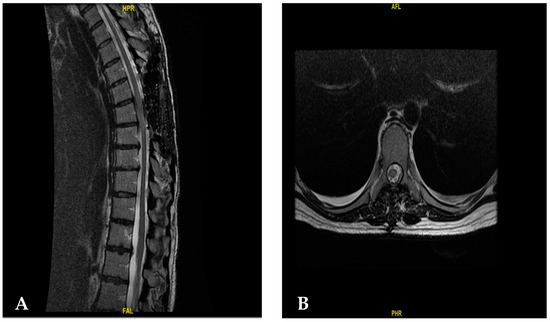

| [30] | 55/Female | T6–T8 | 2-year progressive back pain Weakness on both legs | T6–T8 laminectomy | Angiomatous meningioma | Improvement of motor weakness |